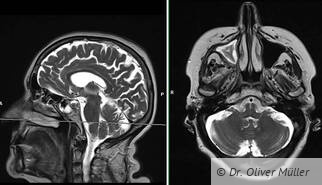

Röntgen – heute und in Zukunft